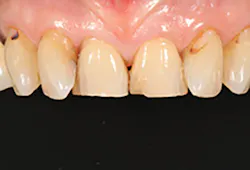

A 67-year-old female executive presented after becoming very self-conscious about the appearance of her anterior teeth (figure 1). During the consultation appointment, a thorough examination was performed, and scanned intraoral 3-D images and impressions (Trios, 3Shape) were obtained. Both arches and the bite registration were scanned (figure 2).

Figure 1: Preoperative retracted view of a female patient’s maxillary anterior teeth showing lingually positioned central incisors due to severe crowding of her arch